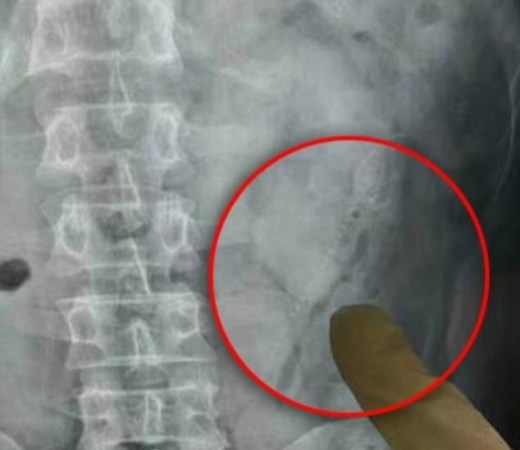

Лекарите направили и рентгенова снимка на мъжа, за да установят къде са рибите. Едната от тях била с дължина от 15 сантиметра.